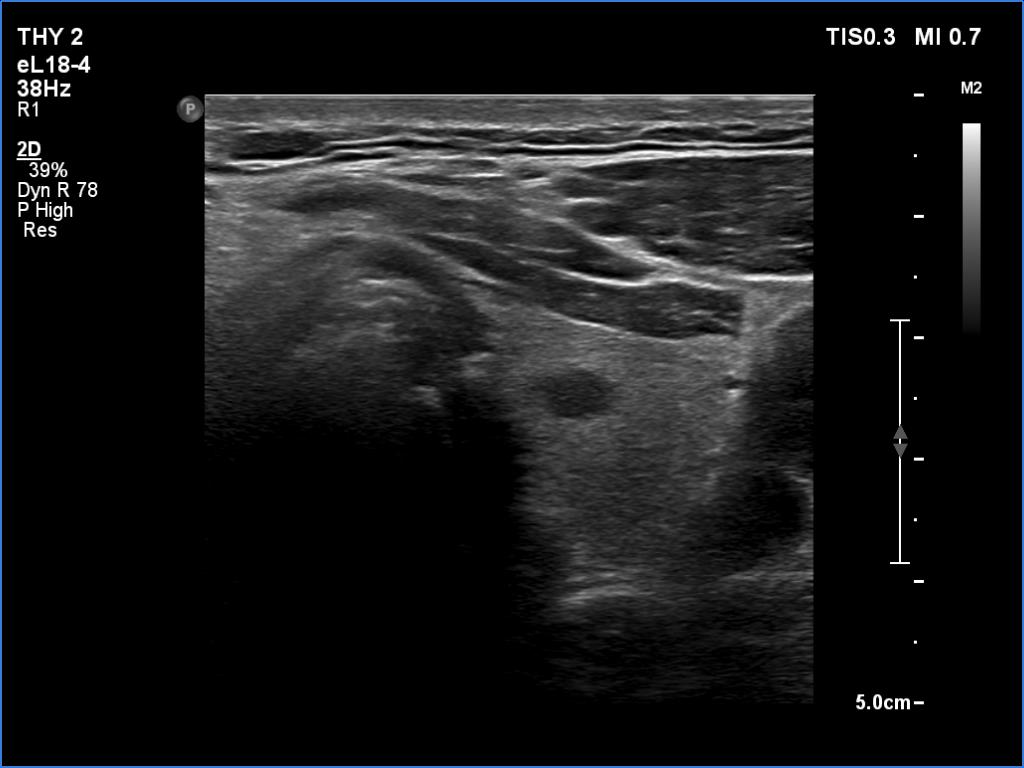

Right lobe, longitudinal scan

Middle third of the left lobe, transverse scan. Here's a hypoechoic discrete lesion.